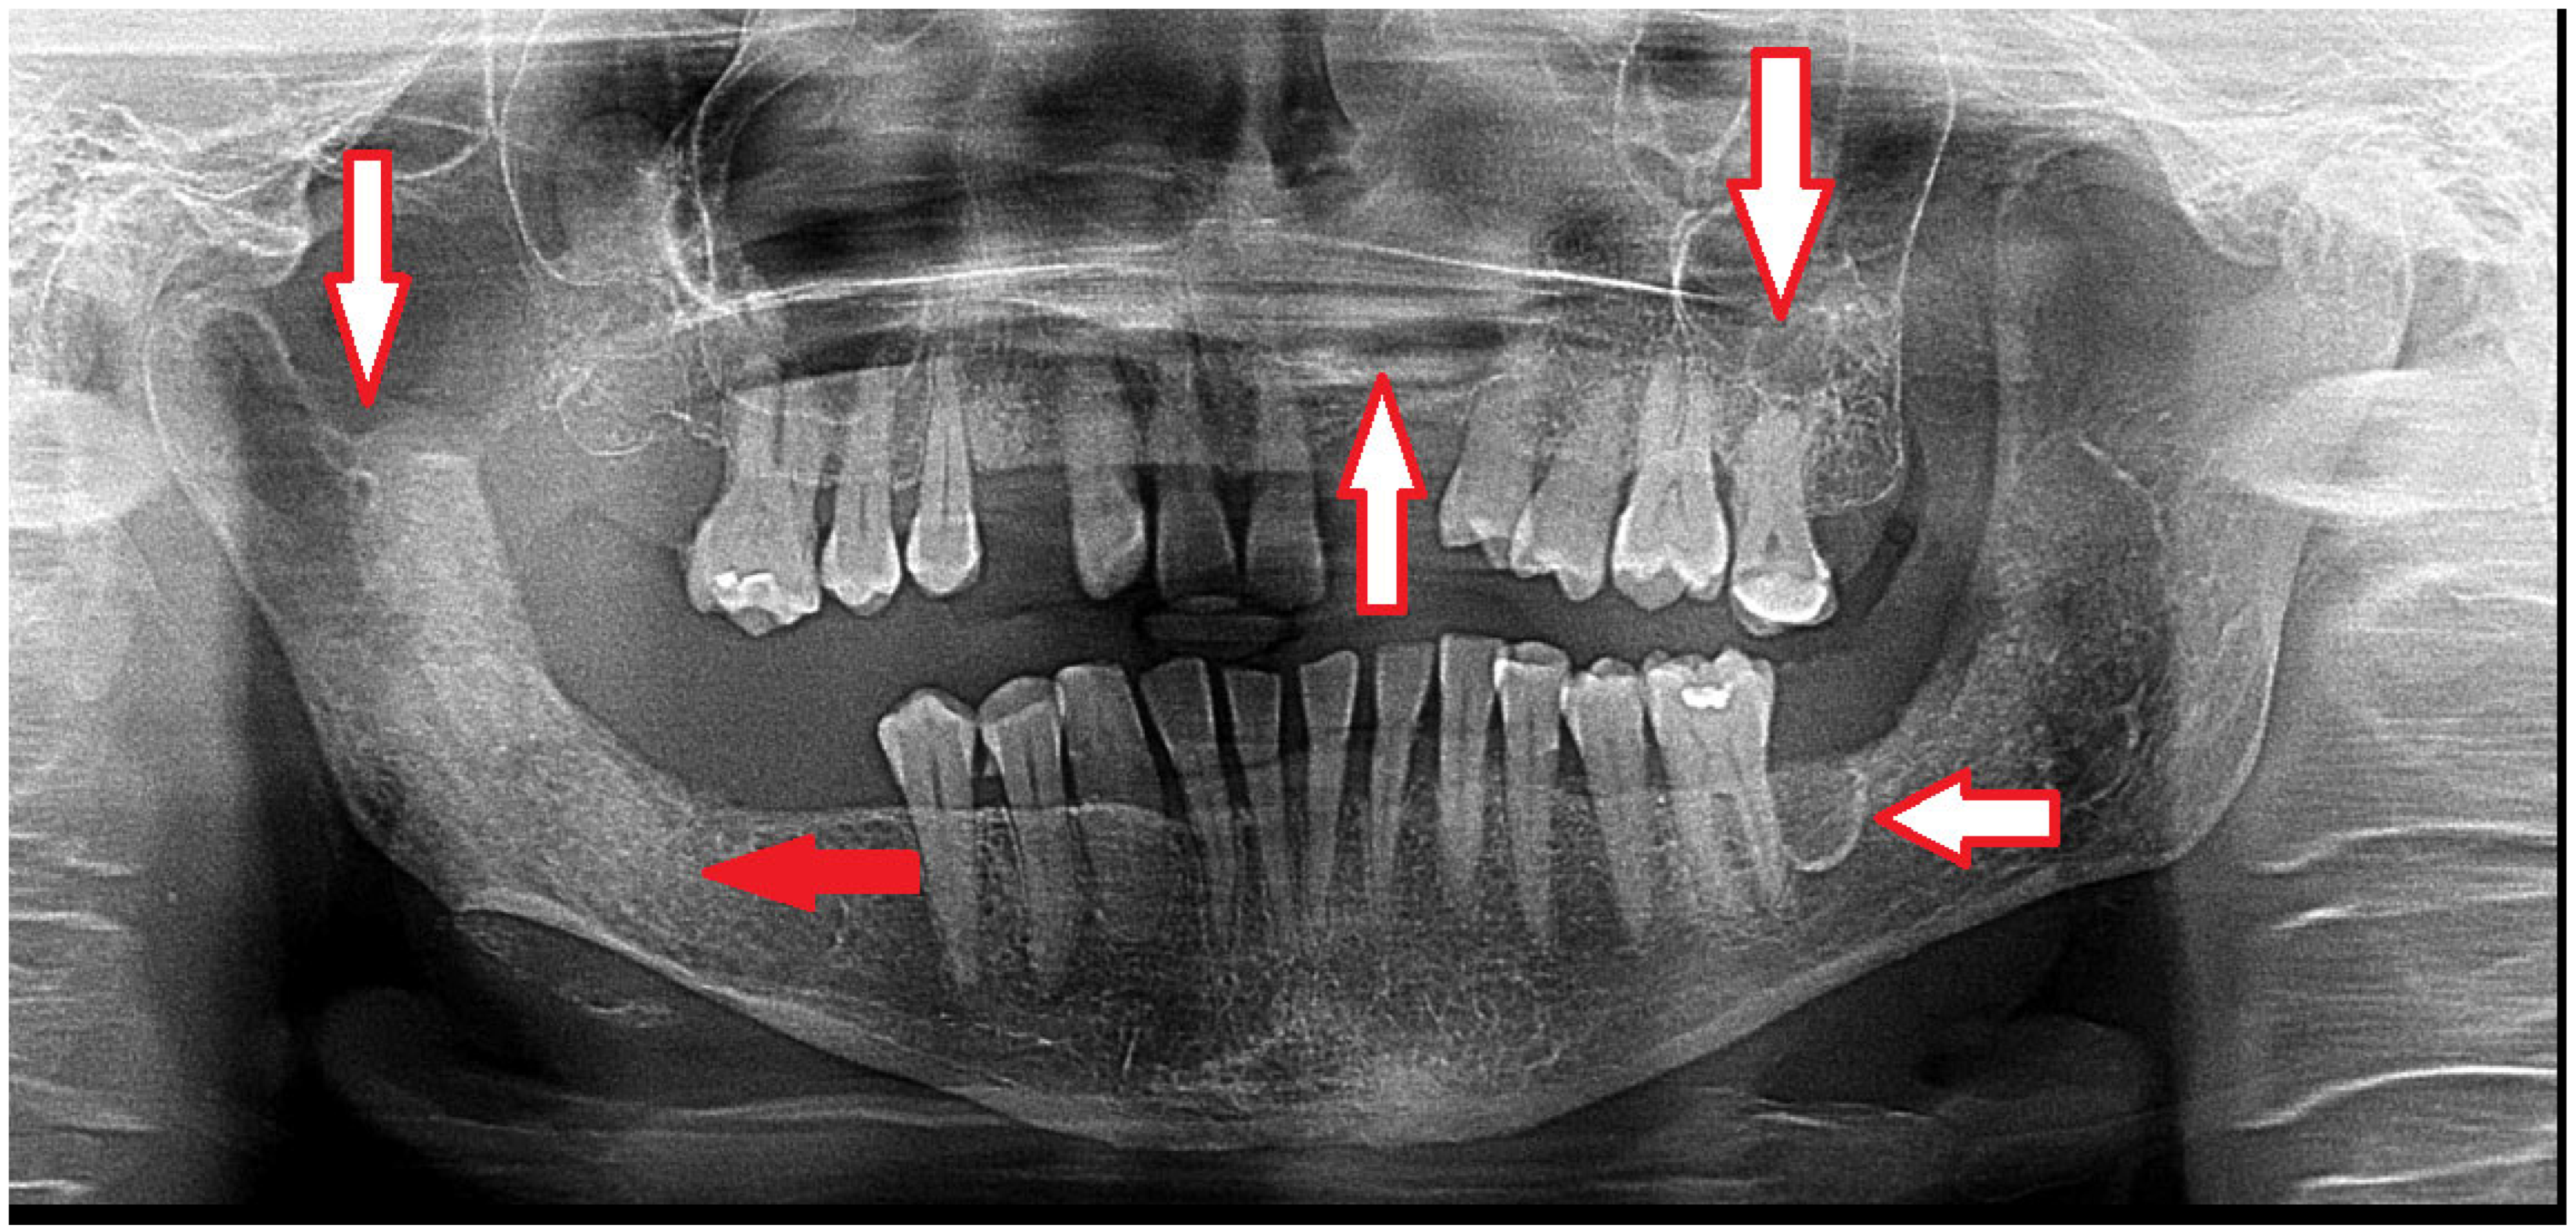

Figure 1. Gorlin-Goltz syndrome (GGS—Nevoid basal cell carcinoma syndrome, NBCCS) can be confirmed because of the occurrence of multiple odontogenic keratocysts (OKCs) in the mandible and maxillary bones (white arrows). This condition has many clinical and radiological characteristics. Because of the PTCH1 gene (a protein called patched-1) mutation, GGS can be present in different expression scales among patients. A standard OPG can easily detect some cystic lesions in jaw bones; however, CBCT (cone-beam computed tomography) is more accurate and precise in evaluating the shape, size, occurrence, and structure of each cyst. Radiologically, the occurrence of multiple cysts might suggest GGS; however, a histopathological evaluation should confirm the occurrence of OKCs after a biopsy (red arrow). Small cysts can be treated with a great success rate; however, some recurrences are possible [1]. In the CBCT, some cyst ranges and bone changes might be more visible, which would then influence the type of surgical approach that might be suitable for each case. In some cases, two-stage surgery consists of cyst decompression and the promotion of new bone growth. The presented panoramic radiograph also shows a significant mixed radiolucent–radiopaque lesion at the right condylar process and condylar head. A biopsy is always mandatory to confirm the final diagnosis and schedule the most adequate approach.